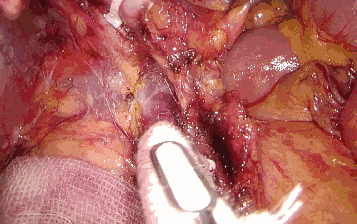

二、保护指引作用

直肠手术中,拓展开内侧的Toldt间隙后,把小纱布放在输尿管和生殖血管之上,可以在切开乙状结肠左侧粘连时,避免损伤上述组织器官。